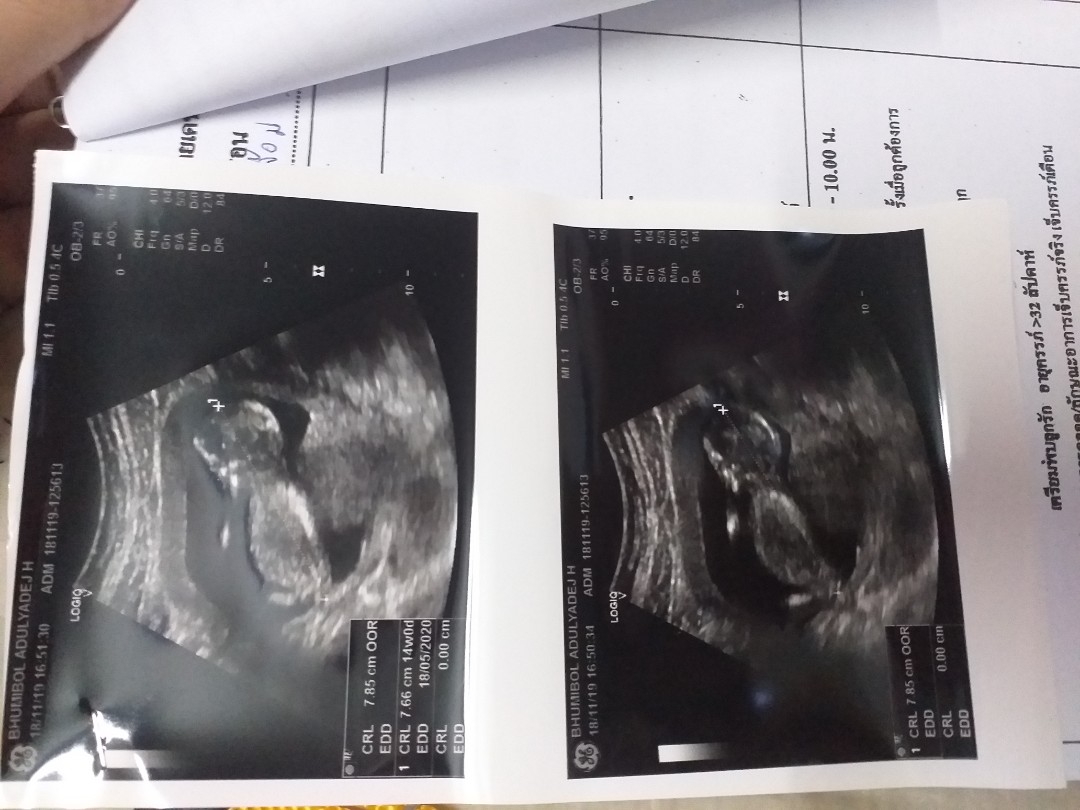

14 วีคค้ะ